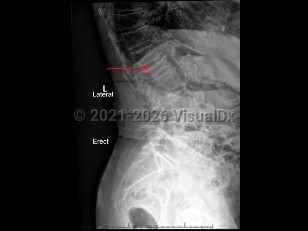

Renal calculus